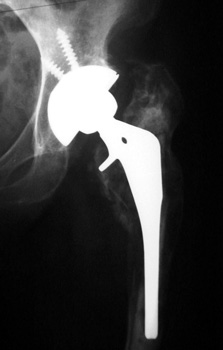

Revision arthroplasty with long femoral stem and large phalanged cup. Note inguinal hernia containing bowel.